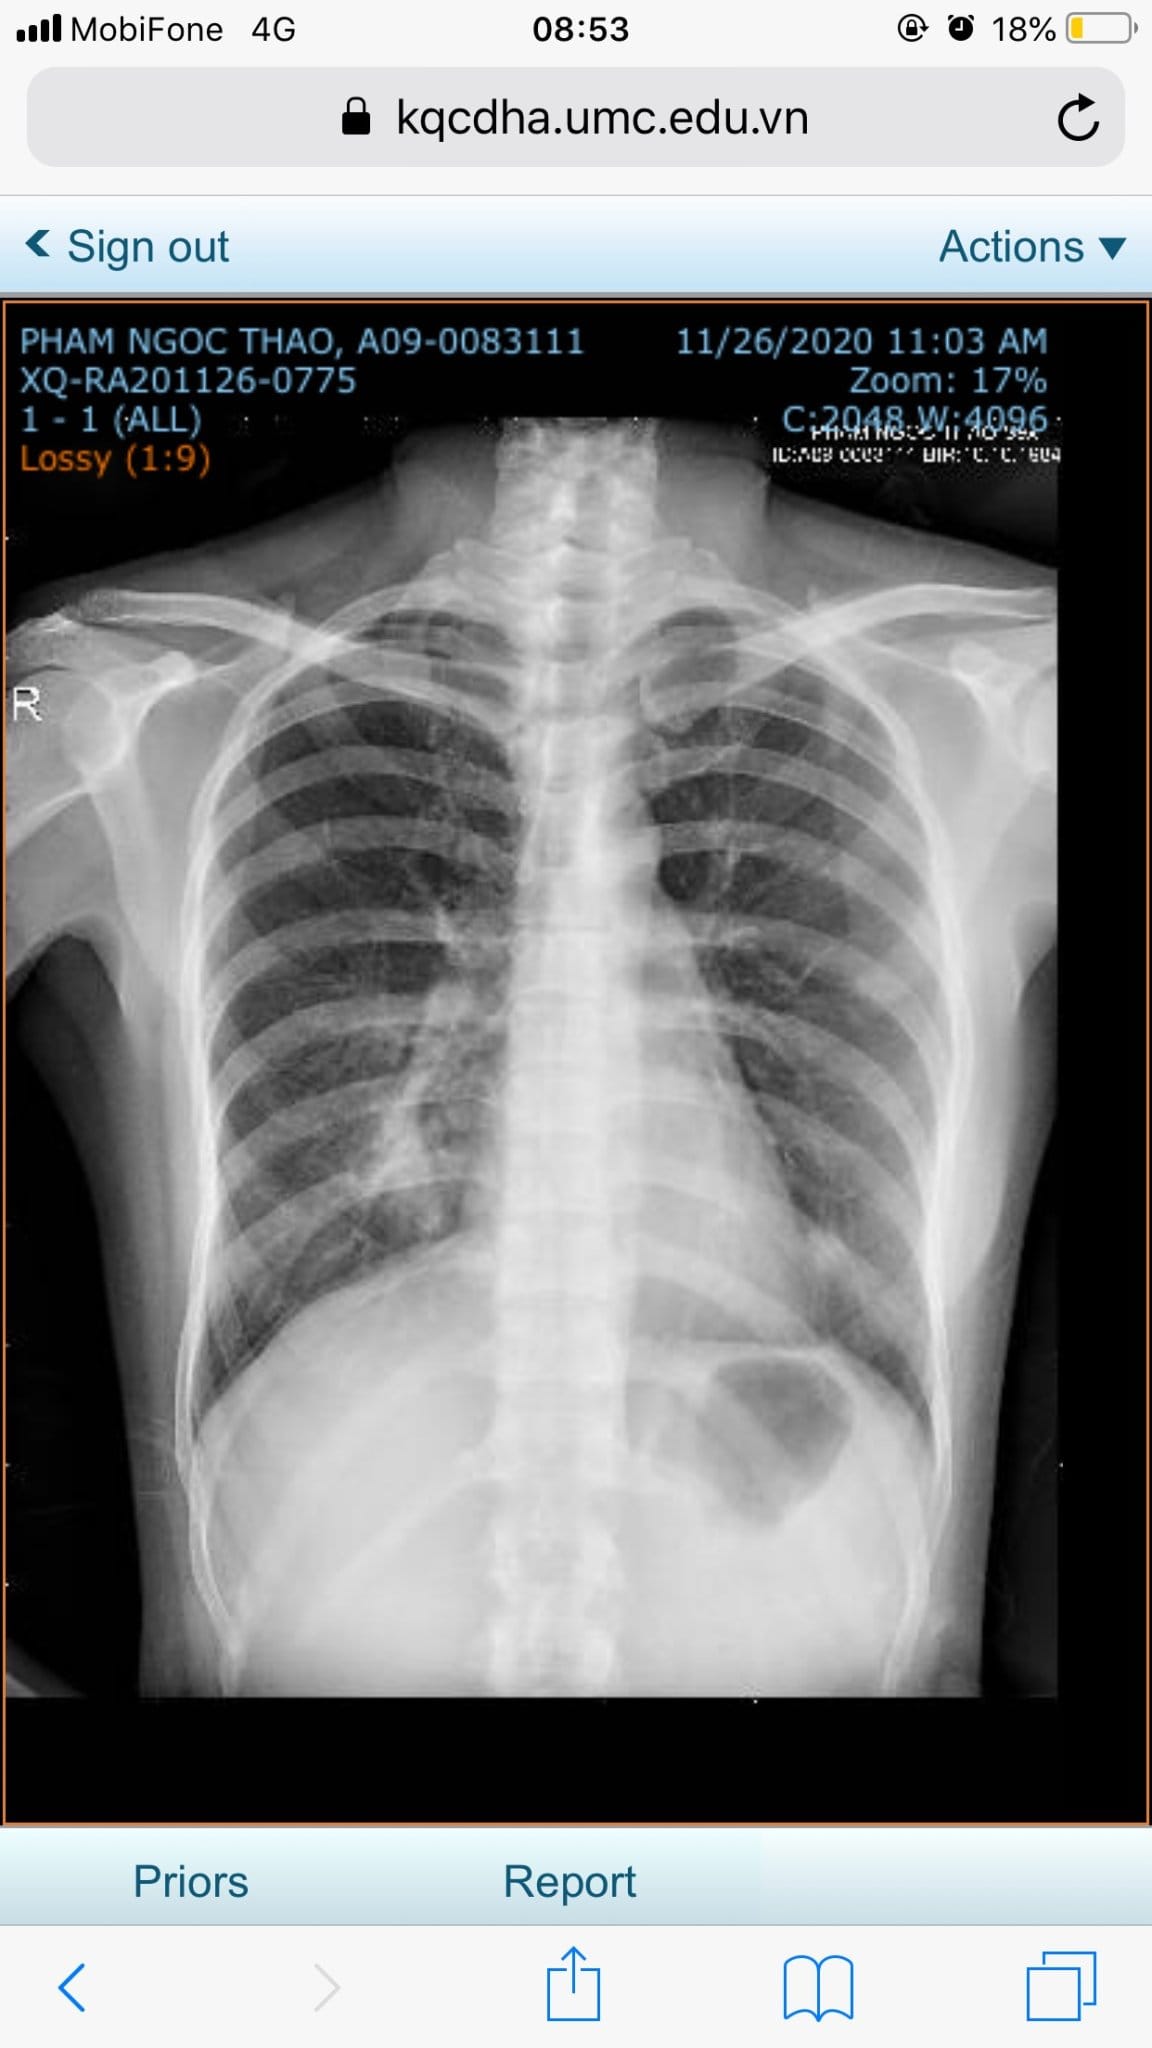

Kết quả X quang của bệnh nhân trước khi chăm sóc sức khỏe bằng Năng lượng sinh học vào ngày 26/11/2020